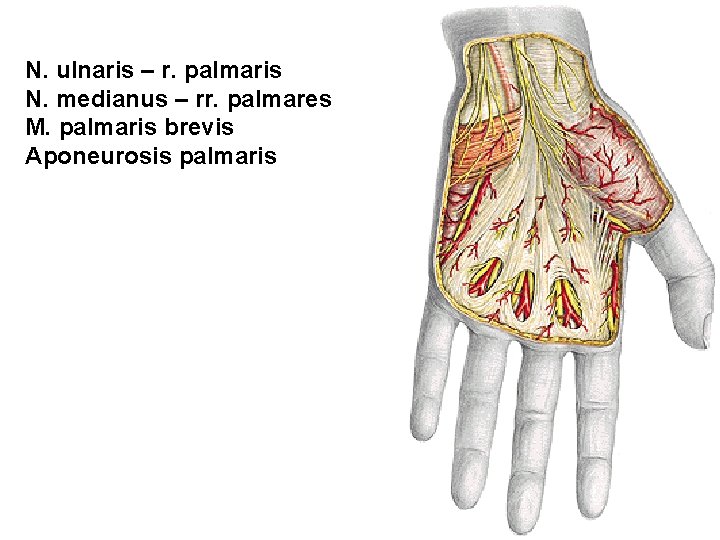

N. ulnaris – r. palmaris N. medianus – rr. palmares M. palmaris brevis Aponeurosis palmaris